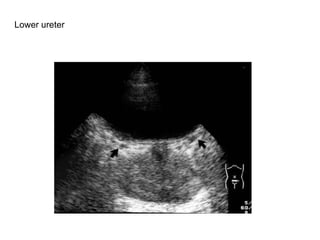

Lower ureter